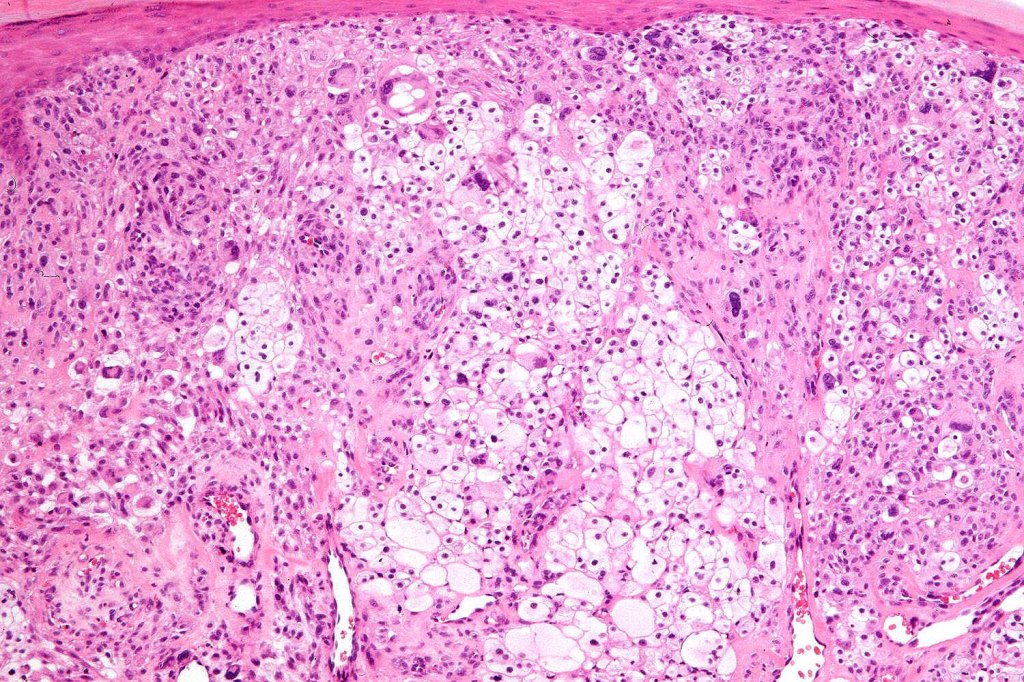

Histological features

•May affect the tumor in part or whole

•Enlarged cells with copious eosinophilic, foamy or clear cytoplasm (some authors include melanoma with clear cell change in the same category)

•Variable pigmentation

•Nuclei vesicular or hyperchromatic

•Pleomorphism is not generally marked and indeed can be very subtle

•Variable mitotic activity